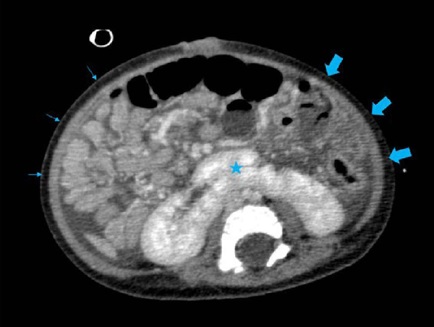

Showed medialized liver and absence of inferior vena cava (IVC) intrahepatic segment. Infrahepatic portion continuing with the azygos system at the thoracic cavity level (Figure 3). Also, ectasia of the splenomesenteric venous circulation, and hepatic and superior mesenteric arteries, polysplenia, and intestinal malrotation (Figures 4 and 5).

Not identifed the portal vein inferring agenesis, with mesenteric-caval communication at renal venous drainage level, as shown in Figure 3. There were signs suggestive of hepatic peribiliary fibrosis (at the expense of focal intrahepatic bile duct ectasia) and moderate ascites, typical findings related to Abernethy type I malformation.